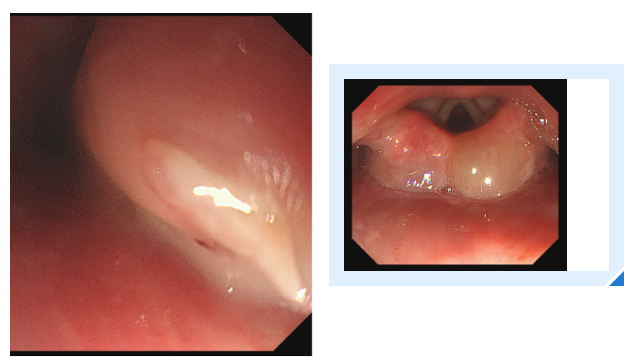

消化内镜室迅速启动取刺准备,当胃镜缓缓抵达食管入口时,清晰可见一根长约3cm的鱼刺,正斜斜嵌顿在食管入口的右侧壁,鱼刺尖端已刺入黏膜下层,周围黏膜因刺激出现明显充血水肿。更棘手的是,鱼刺恰好卡在食管入口的生理拐弯处,这个部位是食管与咽喉的衔接点,角度刁钻,内镜难以稳定固定位置。

操作医生首先尝试使用常规透明帽辅助取刺。透明帽顺利扩张开食管入口,将鱼刺完整暴露在视野中,但当异物钳从内镜操作通道伸出时,问题出现了:由于食管拐弯的角度限制,内镜操作通道与鱼刺的位置夹角过小,异物钳的活动空间被严重压缩。医生反复调整内镜角度和异物钳方向,要么视野被遮挡无法看清鱼刺,要么异物钳无法精准对准鱼刺主体,尝试了数次后,始终无法牢固夹持鱼刺,首次取刺宣告失败。

一切准备就绪后,医生再次为陈女士进行内镜操作。胃镜带着改良后的透明帽缓缓进入食管入口,当鱼刺出现在视野中时,吕主任轻轻旋转胃镜角度,将透明帽的豁口精准对准鱼刺嵌顿的位置。随后缓慢推送胃镜,让鱼刺的一部分稳稳地进入豁口内——此时豁口如同一个“固定卡槽”,将鱼刺牢牢固定住。

紧接着,异物钳从内镜通道中缓缓伸出,借助豁口提供的充足空间,异物钳以最佳角度顺利接近鱼刺,精准地夹住了鱼刺。医生确认夹持牢固后,保持异物钳与胃镜轴线平行,缓慢退镜。退镜过程中,透明帽始终包裹着鱼刺,有效避免了鱼刺尖端划伤食管壁。当胃镜退出口腔时,那根让陈女士痛苦不已的鱼刺被完整取出。